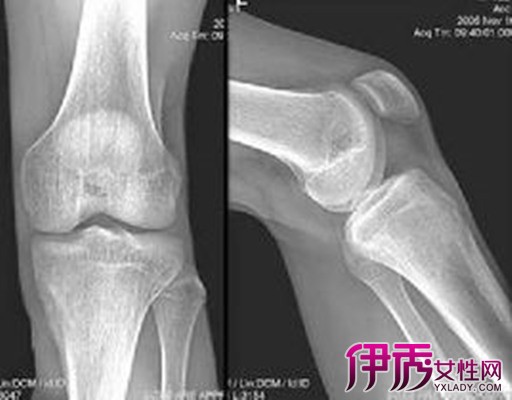

纤维性骨皮质缺损又称干骺端纤维性缺损,是一种非肿瘤性纤维性病变。现认为是儿童发育期的正常变异,多能自行消失,少数可家族发病。本病系局部骨化障碍、纤维组织增生或骨膜下纤维组织侵入骨皮质所致。骨缺损区主要由坚韧纤维组织构成。纤维性骨皮质缺损好发年龄为6~15岁,男多于女。典型好发部位为股骨远侧和胫骨近侧干骺端,尤以股骨内、后壁皮质多见,双侧可对称出现。也可见于股骨近端、胫骨远端、腓骨和上肢骨。常无明显症状,少数有间歇性钝疼,劳累后加重。常常为外伤后进行X线检查时发现。局部可有轻微肿胀和压痛,邻近关节不受侵犯。 X线表现:病变可单发或多发,病灶可一处消失而另一处扩大,少数可消退后再出现。表现为皮质表层的不规则骨缺损,正位像多呈圆形或长圆形,侧位呈水滴状或杯口状,直径多小于2cm。少数病灶内可有粗细不均的致密索条,使病灶呈多囊状改变。边缘清晰,有薄层硬化边,一般无骨膜反应。